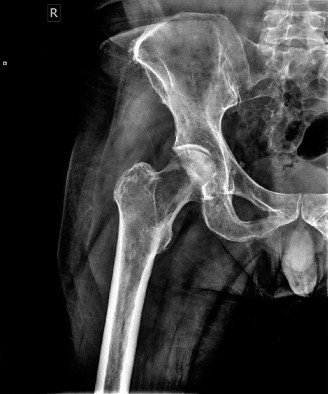

Immediate plain radiographs of the left hip were obtained in the emergency department.

Initial X-ray Findings (Left Hip, AP & Lateral):

- These images revealed a severely comminuted subtrochanteric fracture of the left femur.

- Crucially, the bone quality appeared markedly osteopenic with widespread lytic lesions and irregular cortical destruction, particularly pronounced at the fracture site, extending into the intramedullary canal.

- A 'moth-eaten' pattern was distinctly visible in the cortex surrounding the fracture, highly indicative of a pathologic process.

- This radiographic appearance strongly suggested an underlying pathologic fracture.